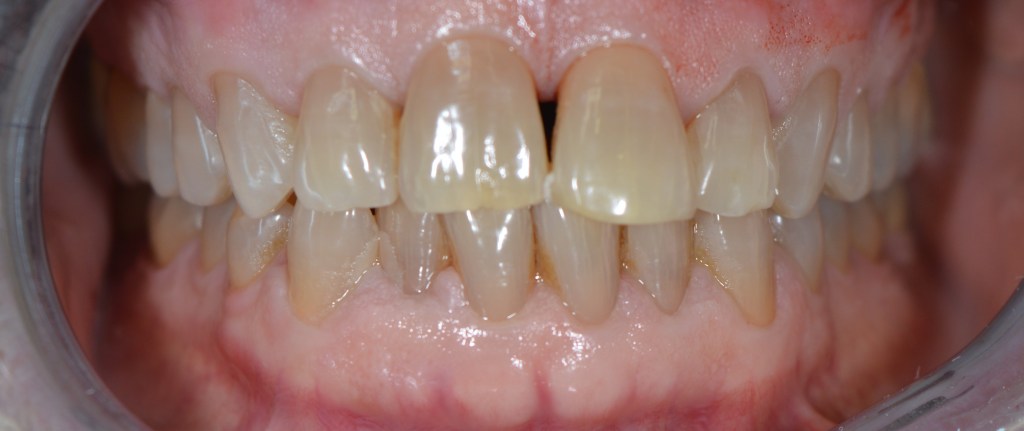

Funkcionális és esztétikai kezelés: harapás korrigálása a fogív kiegyenesítése, fogak közötti rések szűkítése, kereszt harapás megszüntetése az összes megmaradt fog koronázásával. A hiányzó hátsó fogak pótlása implantátumokon megtámasztott koronákkal.

Protetikai munka elkészülésének ideje: 10 munkanap

Koronák anyaga: fémkerámia

Fogszín: A1.